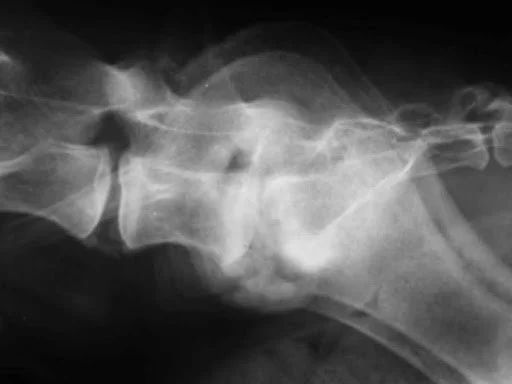

Radiograph of Diskospondylitis in a dog showing affected intervertebral disk.

Lateral projection radiograph of the lumbosacral junction of an 8-year-old MN Labrador Retriever that presented with trouble posturing to defecate, pain, and trouble jumping into the car. The radiograph demonstrates an exuberant proliferation of bony reaction at the LS, sclerosis of the endplates, and lysis of the endplates of the LS disk space.